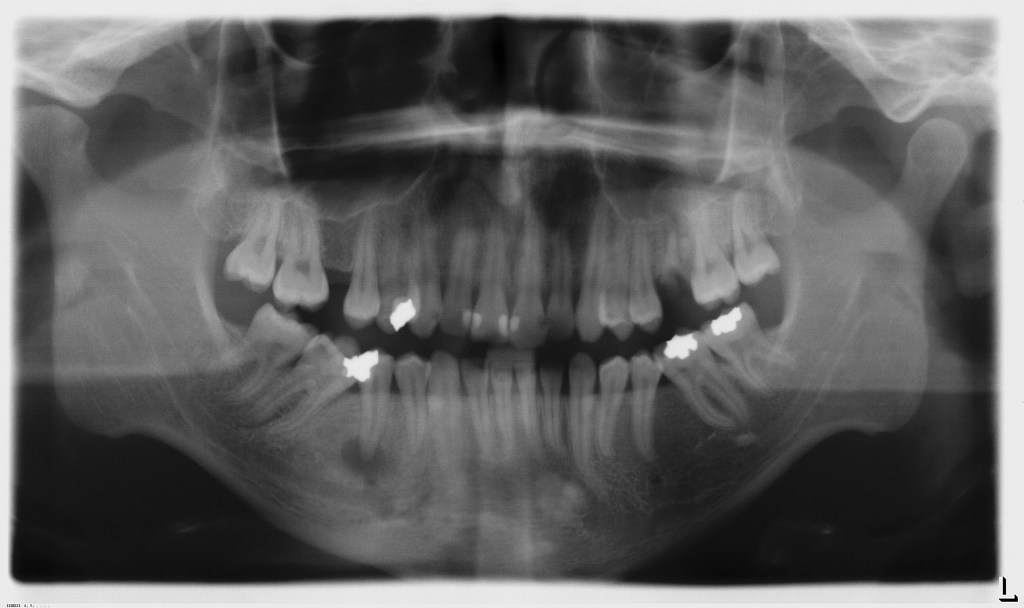

عکس دندان به عصب رسیده